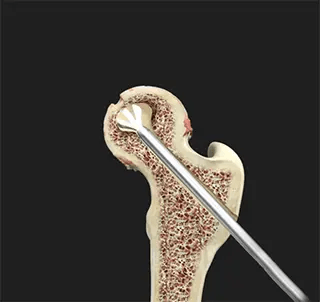

🔹 Decompresia centrală (core decompression):

- Scoaterea „nucleelor” osoase necrotice → stimulează regenerarea osoasă.

- Adesea asociată cu grefare osoasă:

- Autogrefă spongioasă sau alogrefă structurală pentru susținere mecanică și vindecare.

- Augmentare biologică (eficientă doar înainte de colapsul subcondral – stadiul III Steinberg):